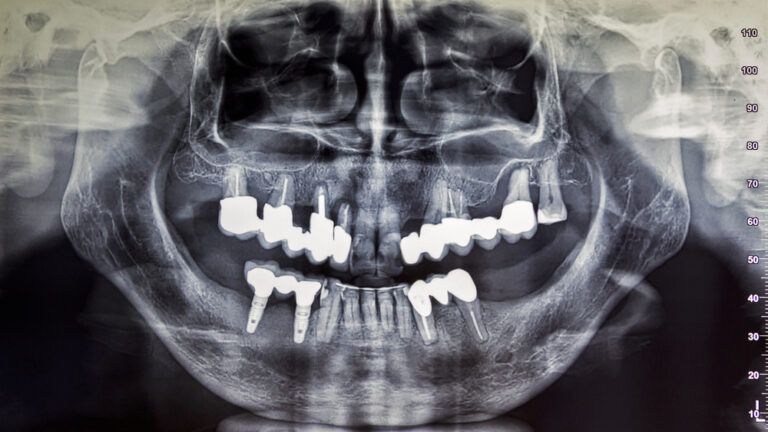

Digital Imaging in Dental Implant Planning

Dental implants have revolutionized modern dentistry, offering a long-lasting solution for restoring function and aesthetics to those with missing teeth. However, the success of these procedures depends heavily on careful planning and precision. Enter digital imaging—a game-changing technology that has